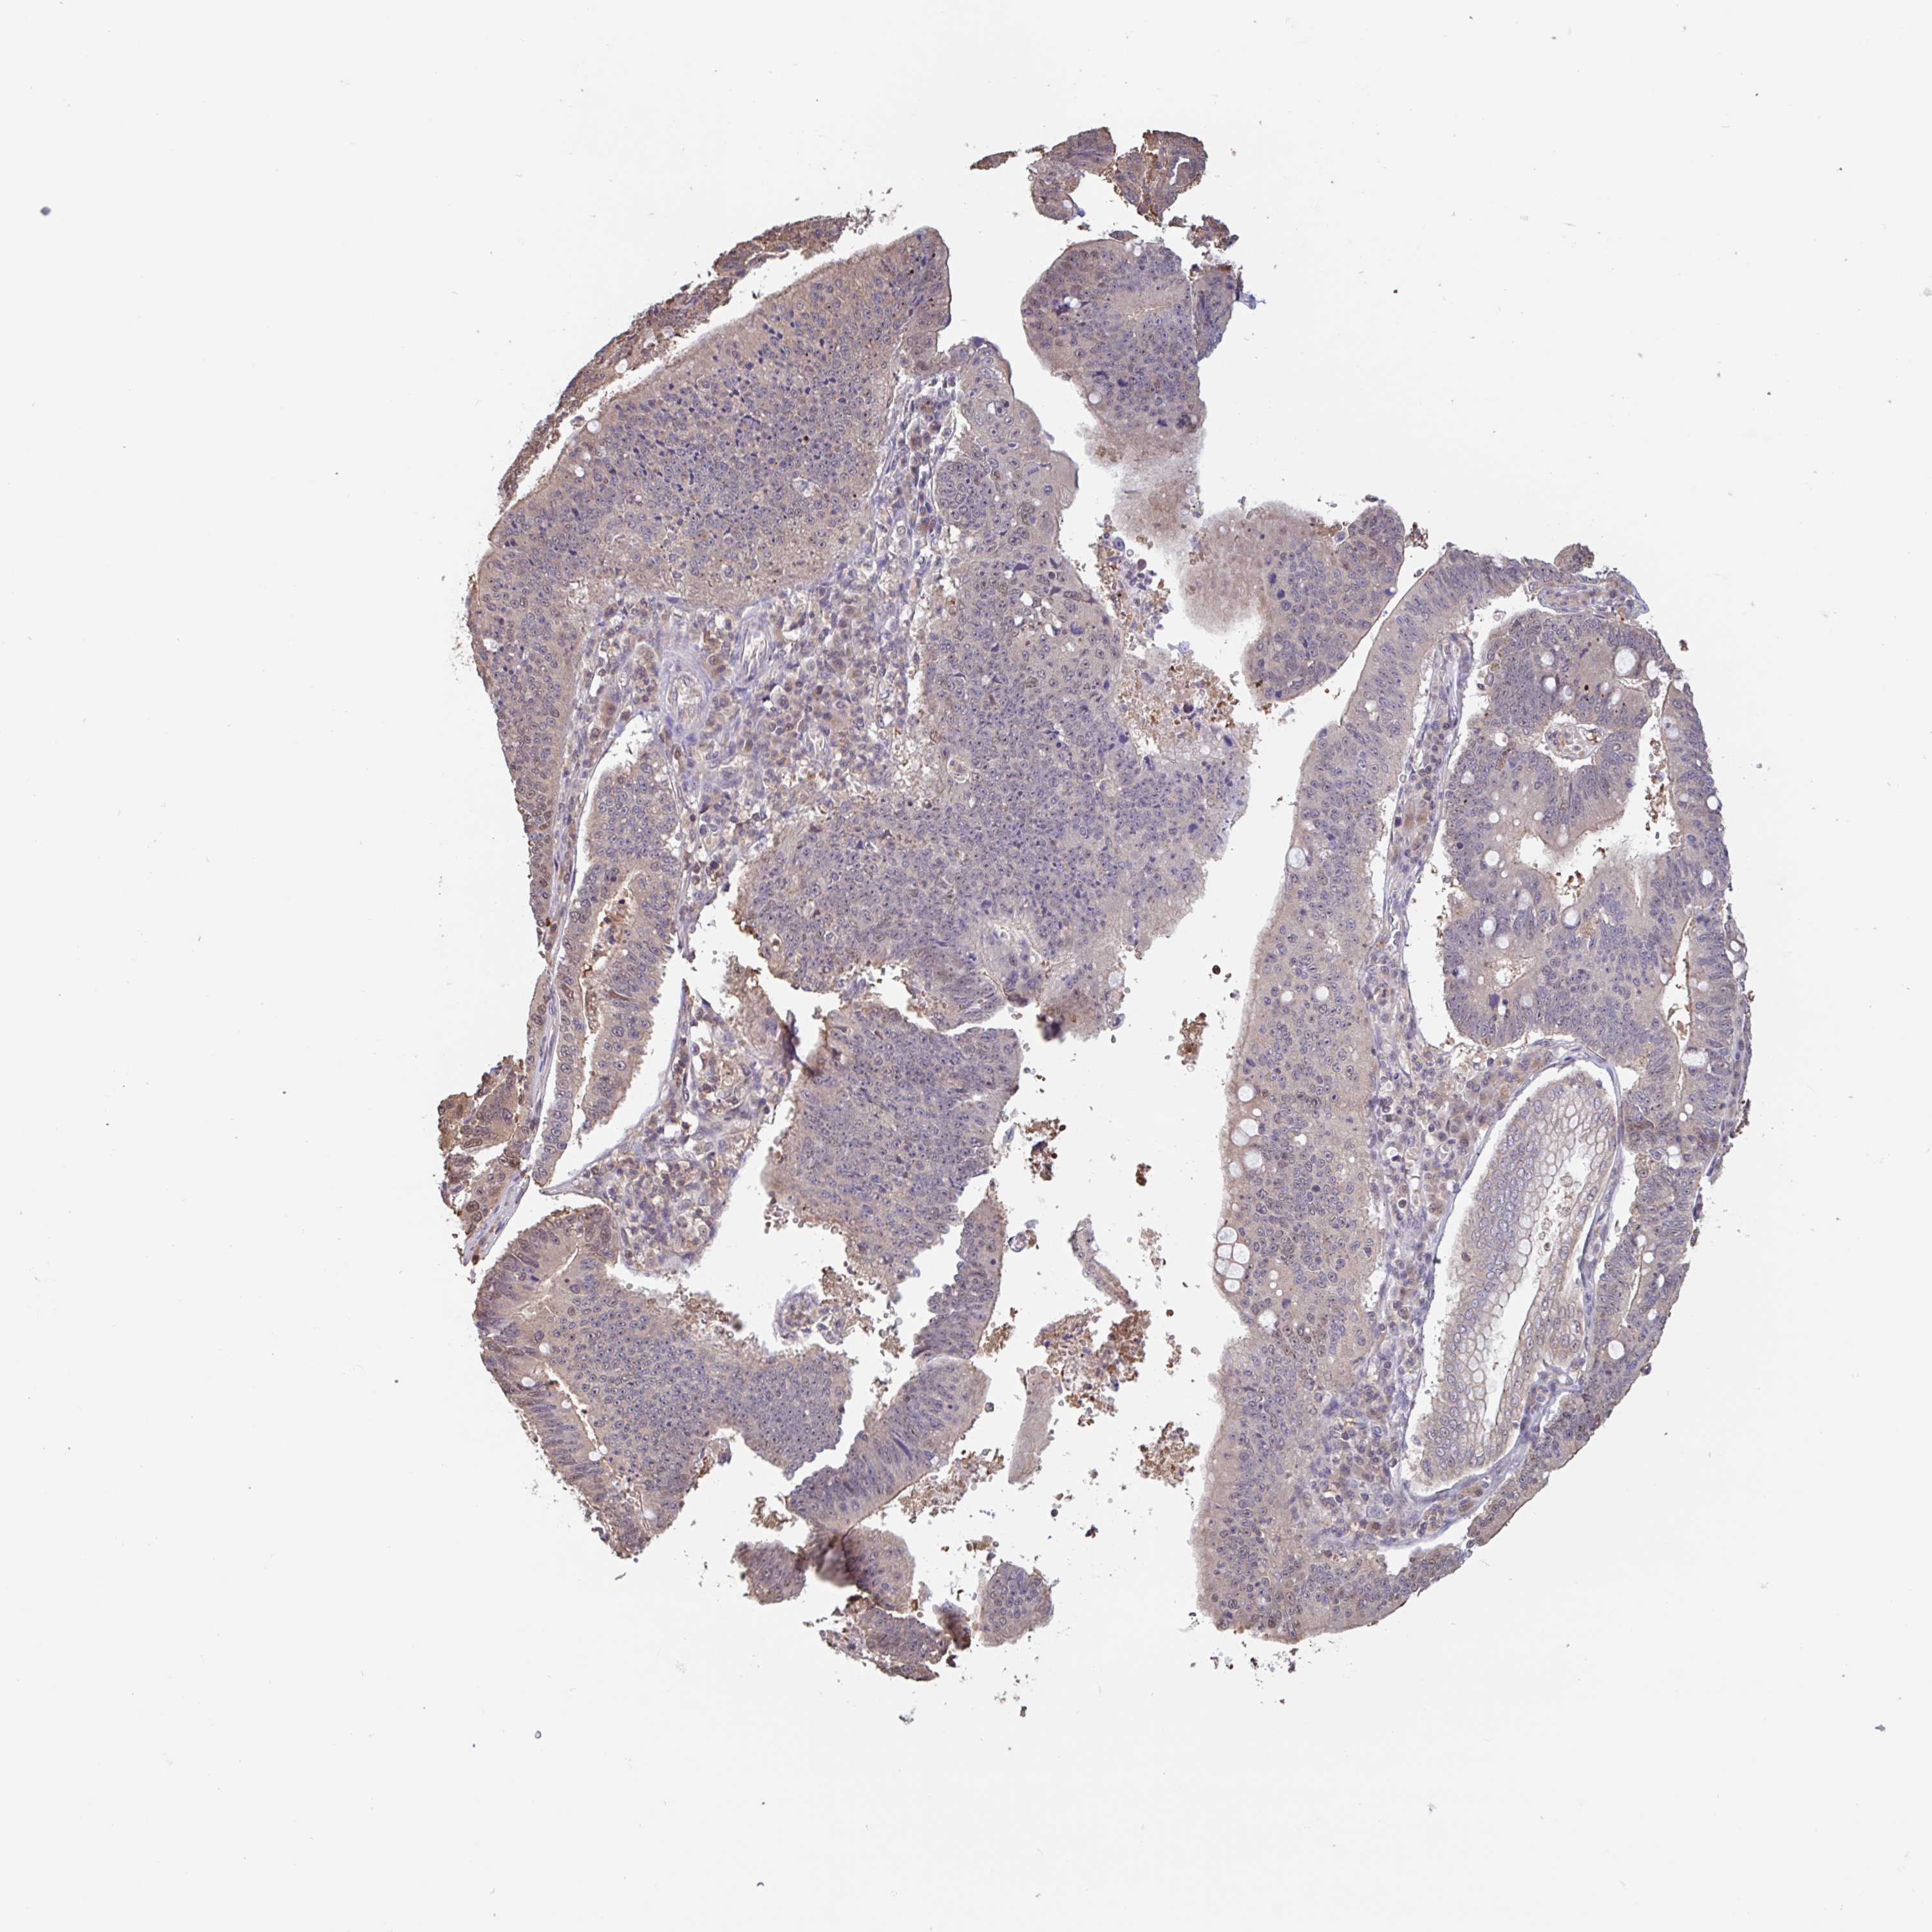

STOMACH CANCER - Protein expressioni

A mouse-over function shows sample information and annotation data. Click on an image to view it in a full screen mode. Samples can be filtered based on level of antibody staining by selecting one or several of the following categories: high, medium, low and not detected. The assay and annotation is described here.

Note that samples used for immunohistochemistry by the Human Protein Atlas do not correspond to samples in the TCGA dataset.

Antibody stainingi

Antibody staining in the annotated cell types in the current human tissue is reported as not detected, low, medium, or high, based on conventional immunohistochemistry profiling in selected tissues. This score is based on the combination of the staining intensity and fraction of stained cells.

Each image is clickable and will lead to virtual microscopy that enables deeper exploration of all samples and also displays staining intensity scores, fraction scores and subcellular localization as well as patient and tissue information for each sample.

Antibody HPA024524

Antibody HPA053090

Staining

High

Medium

Low

Not detected

Intensity

Strong

Moderate

Weak

Negative

Quantity

>75%

75%-25%

<25%

None

Location

Nuclear

Cytoplasmic/membranous

Cytoplasmic/membranous,nuclear

Adenocarcinoma, NOS